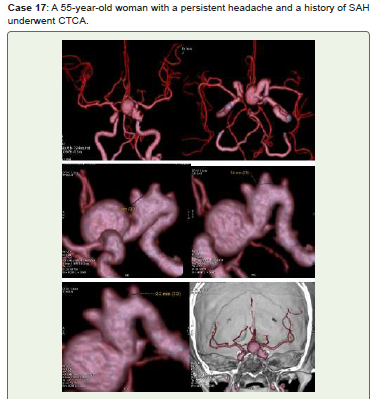

Figure 17:Left ICA bifurcation large saccular aneurysm and three small

saccular aneurysms of terminal communicating ICA (C7) with neck diameters

of 3.7 mm, 3.6 mm, and 2.2 mm are visible in CTCA 3D-VR (A-E) and virtual

dissection of skull (F) pictures. Endovascular therapy and follow-up were

recommended for her.